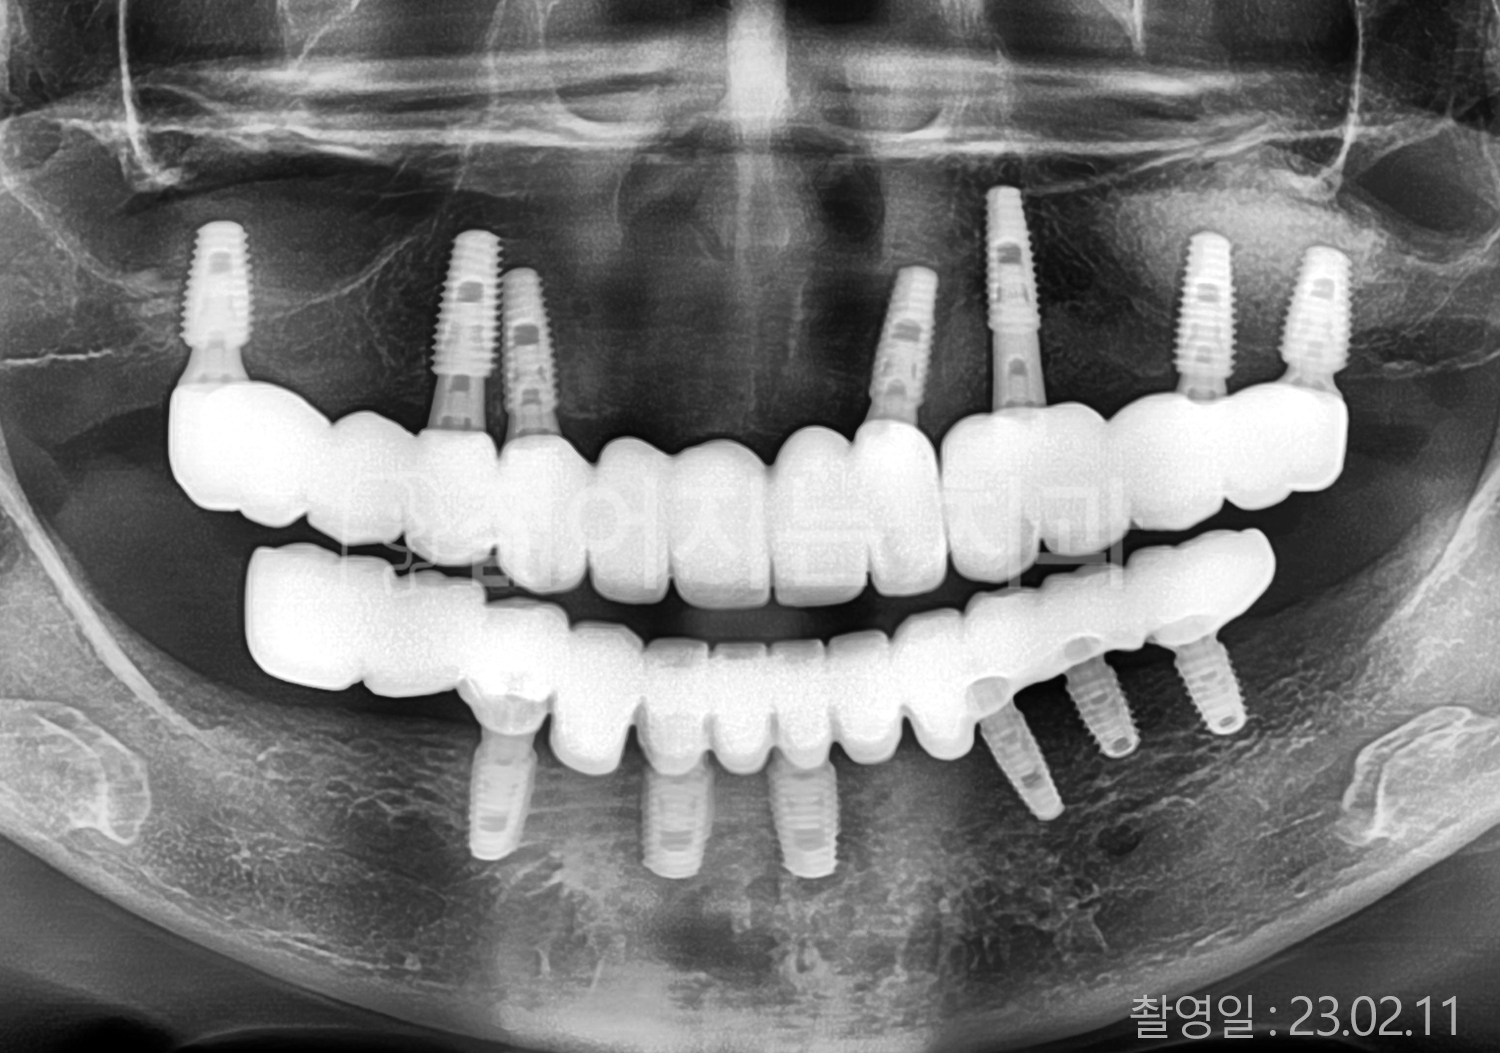

• 60대 고혈압, 고지혈증 전체치아 10개 이상 임플란트

• 70대 전체치아 10개 이상 임플란트

• 60대 전체치아 10개 이상 임플란트

• 50대 전체치아 10개 이상 임플란트

• 50대 고혈압, 고지혈증 전체치아 10개 이상 임플란트

• 60대 고혈압, 당뇨, 고지혈증 전체치아 10개 이상 임플란트

• 80대 고혈압, 당뇨, 골다공증 전체치아 10개 이상 임플란트

• 60대 고혈압 전체치아 10개 이상 임플란트

• 60대 고지혈증 전체치아 10개 이상 임플란트

• 60대 당뇨 전체치아 10개 이상 임플란트